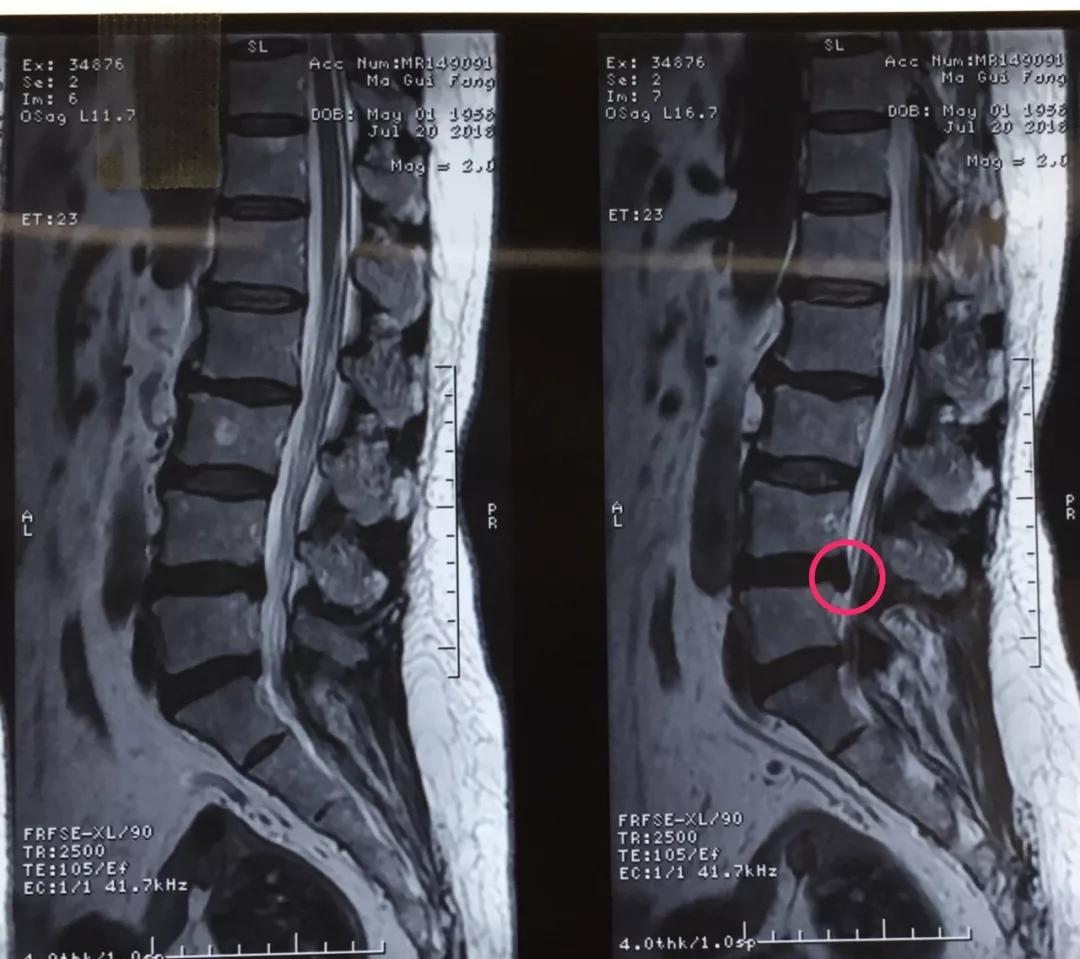

近日,市中心医院骨一科完成了院内首例椎间孔镜日间手术,手术耗时短,痛苦小,术后患者恢复良好。

60岁的人生状态应该是退休在家,带着孙子孙女享受天伦之乐,而同样是60岁的马老太,被腰椎间盘突出症困扰了多年,稍微劳累就腰背酸痛,近几个月来又开始出现左下肢的过电样抽痛,抽的腿都抬不起来,家人带着马老太到医院做了检查说是腰椎间盘突出症,问了几家医院都说要来开刀手术,卧床两月,这下把马老太吓住了,一边是病痛折磨,一边是对手术的恐惧,正绝望之际,邻居建议马老太到91论坛 郭华副院长的专家门诊看一下,马老太并没有抱太大希望,那么多医院都说要手术,估计治疗方案是一样的,手术是免不了了。到中心医院后,郭华副院长仔细地询问了马老太的病史,并进行了细致的查体,然后看了看片子,对马老太说:“你这个情况确实是腰椎间盘突出症,但是不需要全麻开大刀,局麻下1cm小口把椎间盘取出来就可以了,术后就可以直接下地走路了,而且你现在检查齐全了,当天住院、当天手术、当天出院,我们叫做——椎间孔镜日间手术”,马老太半信半疑的回家考虑了几天,最终马老太还是相信中心医院的实力,24日马老太入住骨一科后,郭华副院长、严少荣主任、姬钢主任医师中午共同为马老太局麻下实施了经皮椎间孔镜下髓核摘除术,手术共计一小时,手术完马老太抬腿就不痛了,郭华副院长告诉马老太,你这个情况完全可以出院走路回家了,可把马老太高兴坏了。

郭华副院长介绍:随着人口老龄化,腰椎间盘突出症的发病数量越来越多,而医学的进步也同样日新月异,传统的开大刀手术越来越少,我院开展的经皮椎间孔镜下髓核摘除术(PELD)是近几年来成熟起来地一种微创手术方式,局麻下不到一小时就可以取出压迫神经根的椎间盘,术后即刻解除疼痛下地走路,甚至可以做到日间手术(当日住院、当日手术、当日出院),医保报销后花费少,效果立竿见影,得到了广大患者的认可和好评。希望医学德进步给广大病患带来福音,希望我院的新技术能为更多的病人解除病痛。